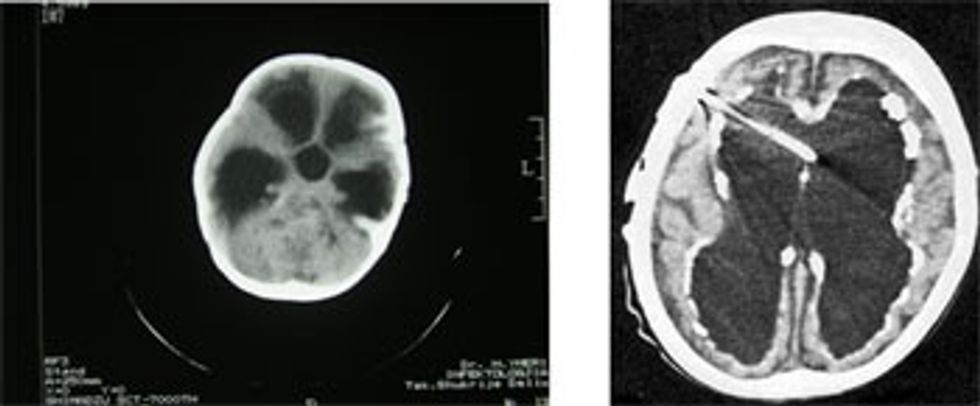

Metodat e ndryshme në diagnostikimin radiografik të hidrocefalusit.

A: Indeksi ventrikular paraqet raportin e diametrit ventrikular në nivelin e brirëve frontalë me diametrin e trurit të matur në të njëjtin nivel. Indeksi ventrikular në të dy rastet është 39%.

B: Rritja proporcionale e brirëve temporal dhe e trupit të ventrikujve lateralë është me gjasë shenja më senzitive dhe më e qëndrueshme në diferencimin e hidrocefalusit prej atrofisë.

C: Këndi ventrikular matë divergjencën nga briu frontal. Në teori, këndi i ndërtuar nga tehu i përparmë ose i epërm i briut frontal në nivel të foramina Monroi është i zvogëluar në rastet e zmadhimit koncentrik të brirëve frontal..

D: Radiusi i bririt frontal paraqet diametrin më të gjërë të brirëve frontal të matur në këndin që mbyllë 90º me boshtin gjatësor të bririt frontal. Dobishmëria e kësaj matjeje demonstrohet me një rritje markante të radiusit të bririt frontal te pacientët me hidrocefalus (lartë) që është e kundërt te pacientët që kanë atrofi cerebrale (poshtë):